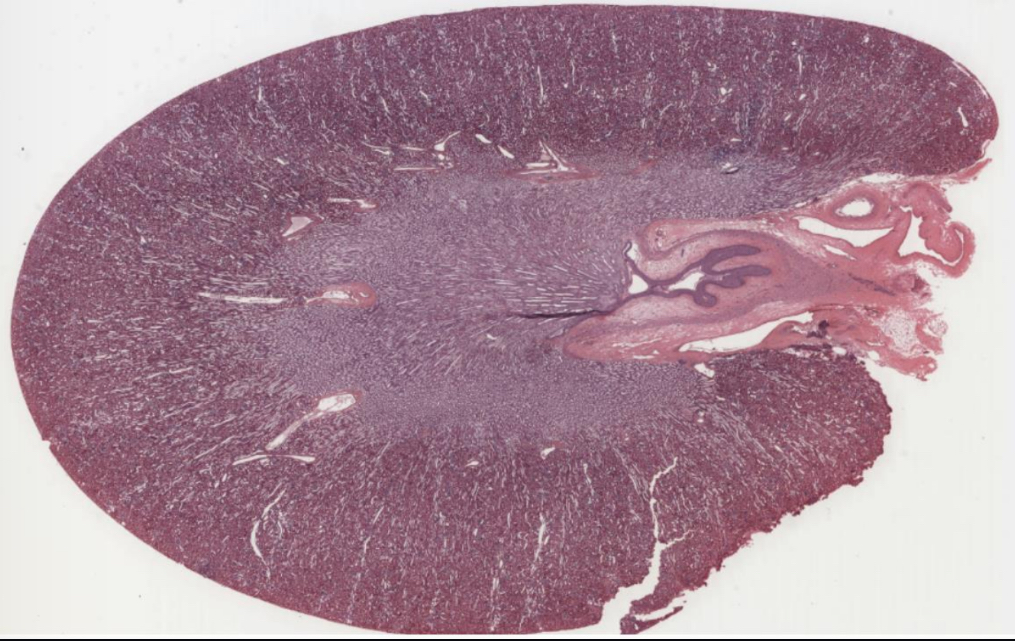

What organ is shown in the picture?

Kidney

Name the structure indicated by A.

Glomeruli

Name the structure indicated by B.

Proximal tubule

Name the structure indicated by C.

Distal tubule